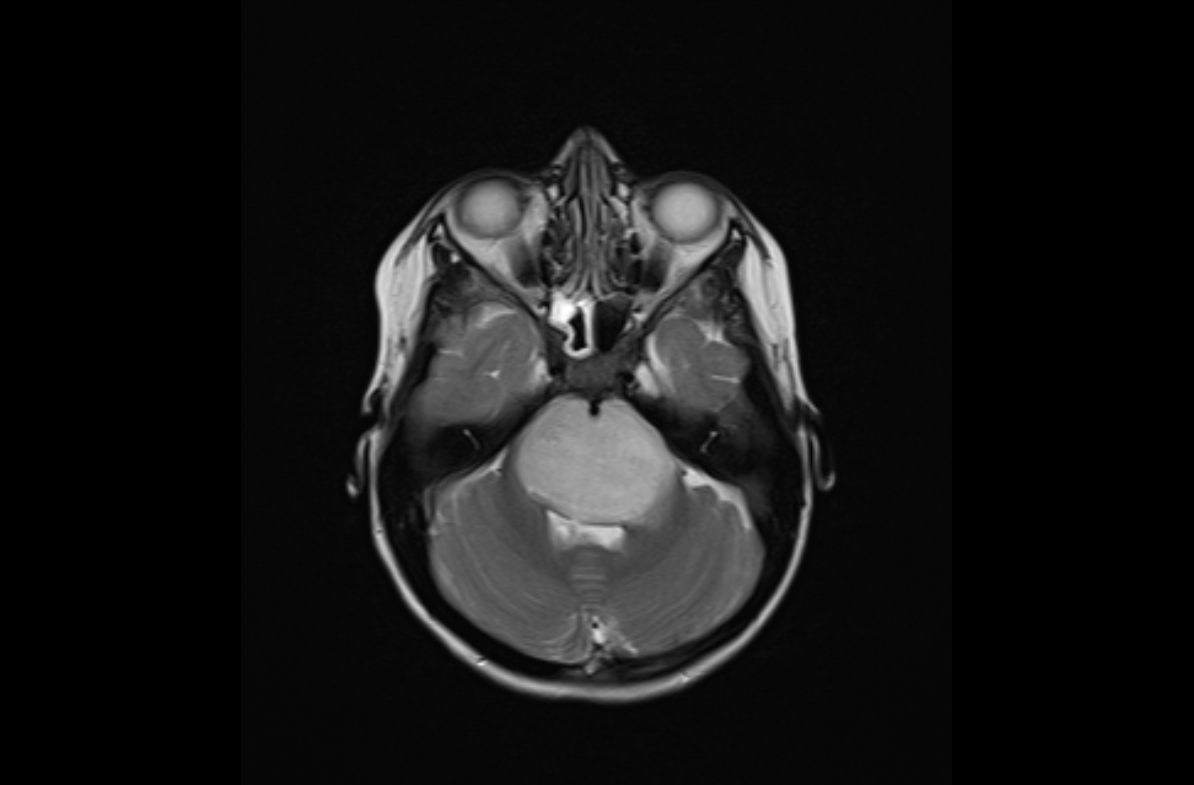

The field of explainability in artificial intelligence has witnessed a growing number of studies and increasing scholarly interest. However, the lack of human-friendly and individual interpretations in explaining the outcomes of machine learning algorithms has significantly hindered the acceptance of these methods by clinicians in their research and clinical practice. To address this, our study employs counterfactual explanations to explore "what if?" scenarios in medical research, aiming to expand our understanding beyond existing boundaries on magnetic resonance imaging (MRI) features for diagnosing pediatric posterior fossa brain tumors. In our case study, the proposed concept provides a novel way to examine alternative decision-making scenarios that offer personalized and context-specific insights, enabling the validation of predictions and clarification of variations under diverse circumstances. Additionally, we explore the potential use of counterfactuals for data augmentation and evaluate their feasibility as an alternative approach in our medical research case. The results demonstrate the promising potential of using counterfactual explanations to enhance trust and acceptance of AI-driven methods in clinical research.